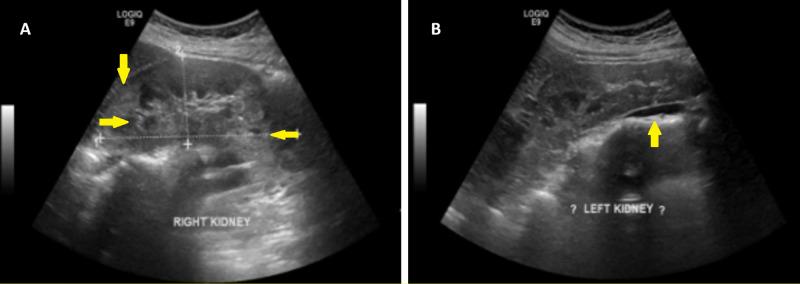

Tuberous sclerosis complex (TSC) is a rare genetic, neurocutaneous condition characterized by hamartomas in different organs, including the brain, skin, heart, kidney, and lungs. Fibromas are the typical presentation, but rare symptoms may present as well. We present the case of a 26-year-old woman who presented to our clinic with long-standing cutaneous manifestations of TSC and lacked the typical neurological and intellectual signs of the condition.